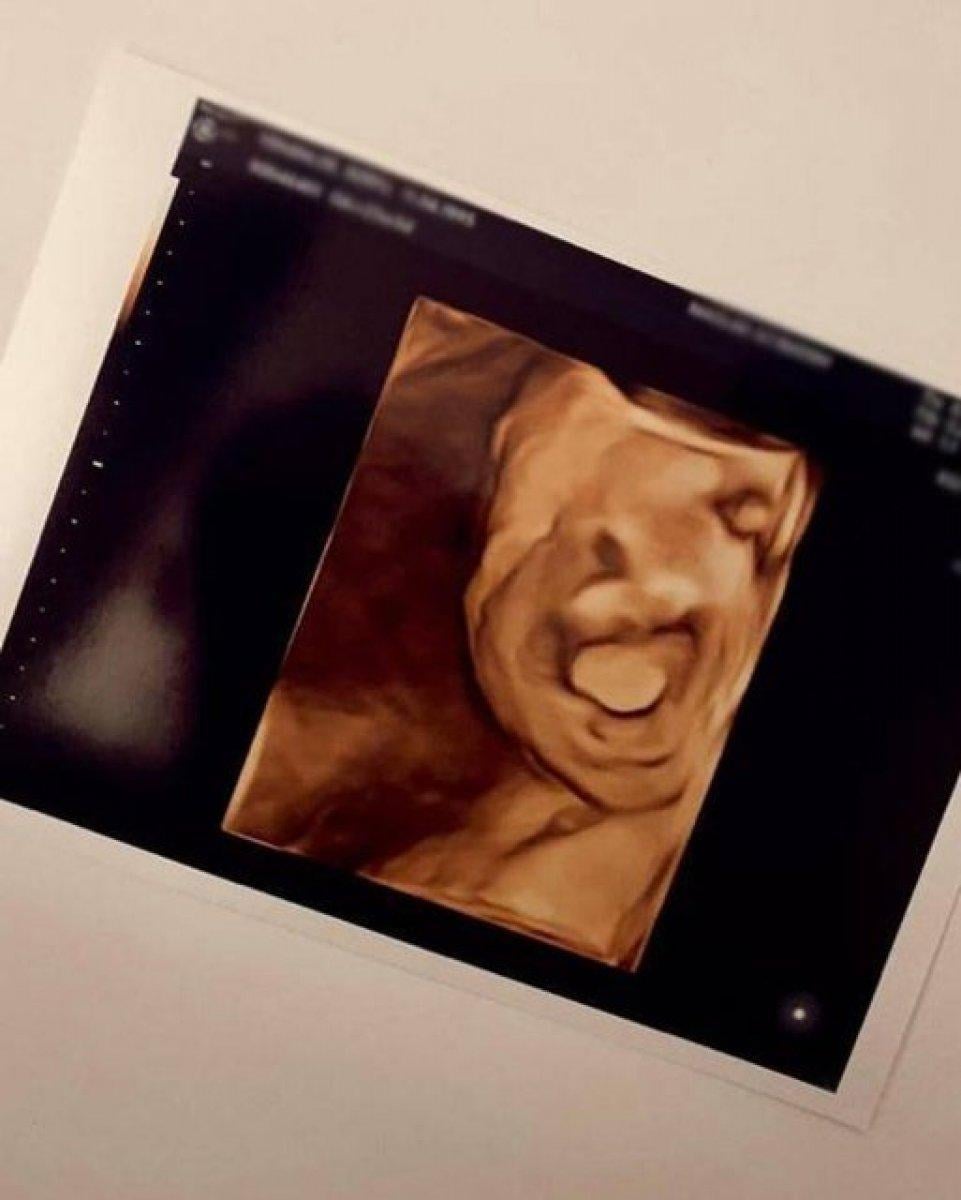

Şimdilerde ikinci kez anne olmaya hazırlanan Berfu Yenenler, Instagram hesabından bebeğinin ultrason görüntülerini yayınladı.

"AYNI BABASI"

Yenenler, gönderisine "Ah Mete emmi güzel yüzünü gösterdi. Burnu yine sana benziyor kocacığım (Eser Yenenler) tebrikler. Bu arada sonuncu fotoğrafta gülmüş siz de gördünüz değil mi?" notunu düştü.